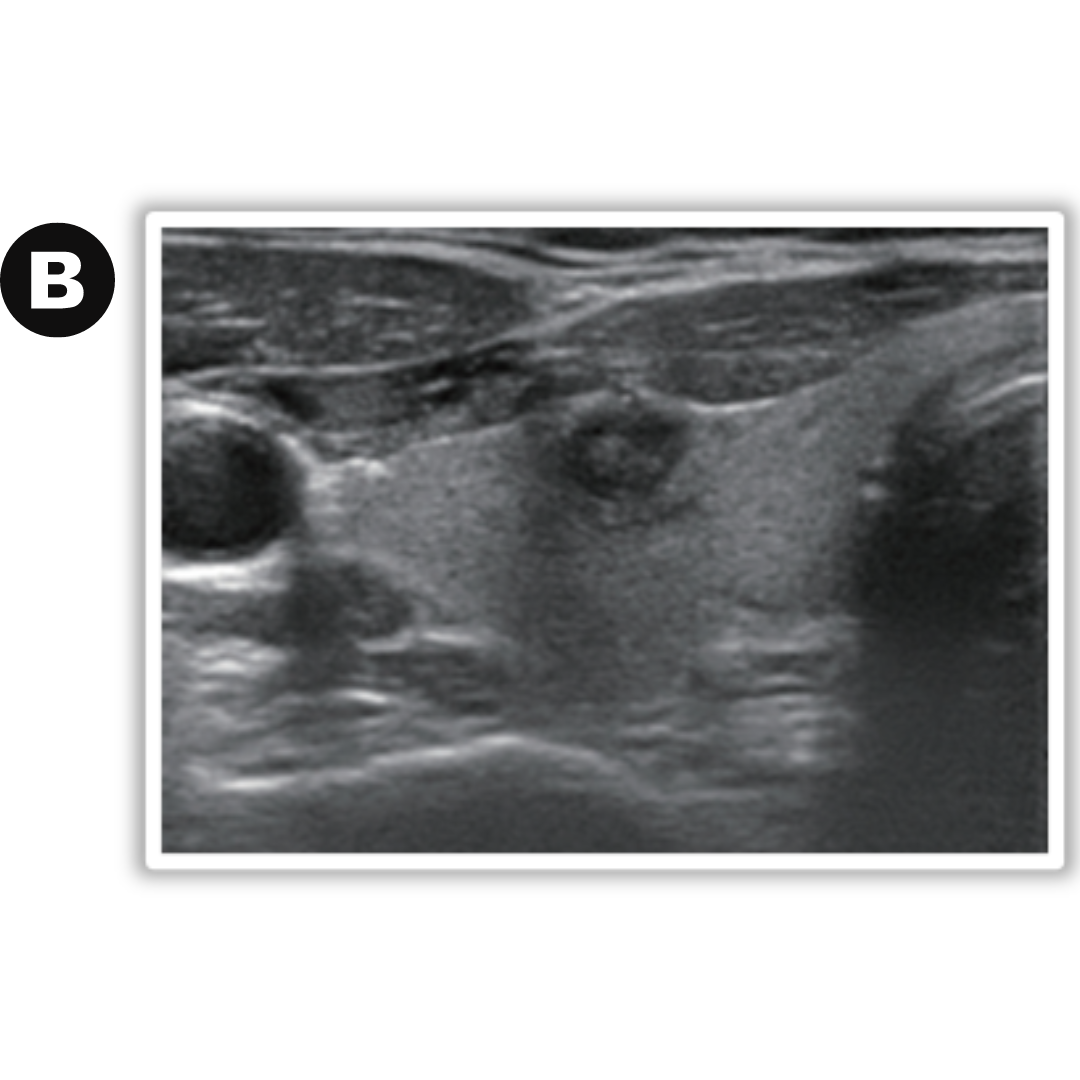

Caso 02: a) Nódulo solido heterogéneo con halo hipoecogénico. b) control a los 3 años siguientes, evidenciando una disminución notoria en su tamaño.